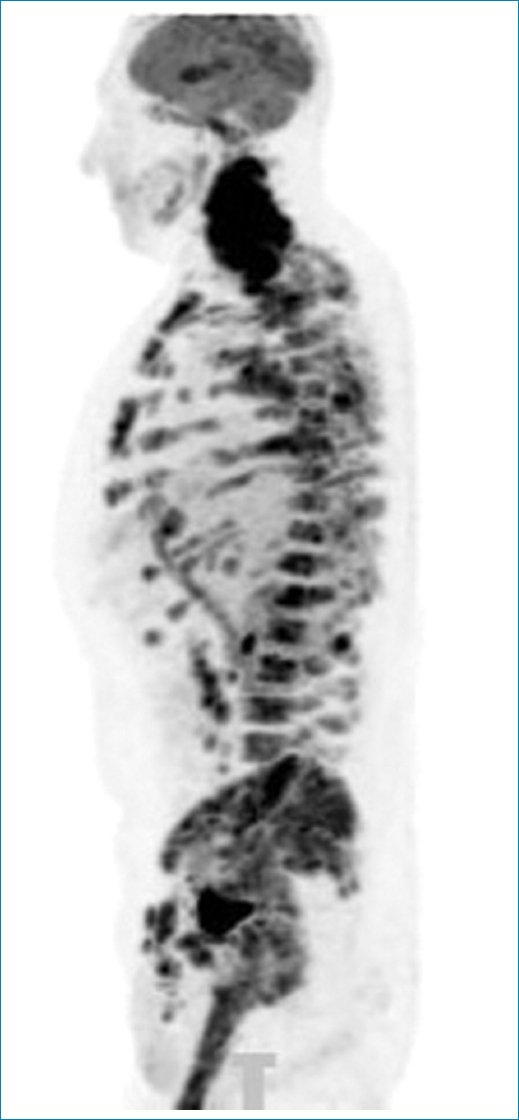

Figura 13. Imagen sagital en MIP de PET-TC que pone de manifiesto el hipermetabolismo de la médula ósea en un caso de linfoma con compromiso ganglionar múltiple y peritoneal.

Estos patrones de LP en la PET-TC se acompañan en general de adenomegalias hipermetabólicas múltiples en diferentes sitios, así como de hipermetabolismo esplénico y de la médula ósea, colaborando para el diagnóstico certero y diferencial con las demás afecciones mencionadas (Figs. 12 y 13). Es importante recordar que la avidez de la 18F-FDG varía según el tipo de linfoma involucrado. Así, los linfomas de alta agresividad presentarán mayor metabolismo glucídico que aquellos linfomas indolentes o de bajo grado, variando también su avidez según el grado de respuesta a la quimioterapia instaurada6,19,21 (Fig. 14).